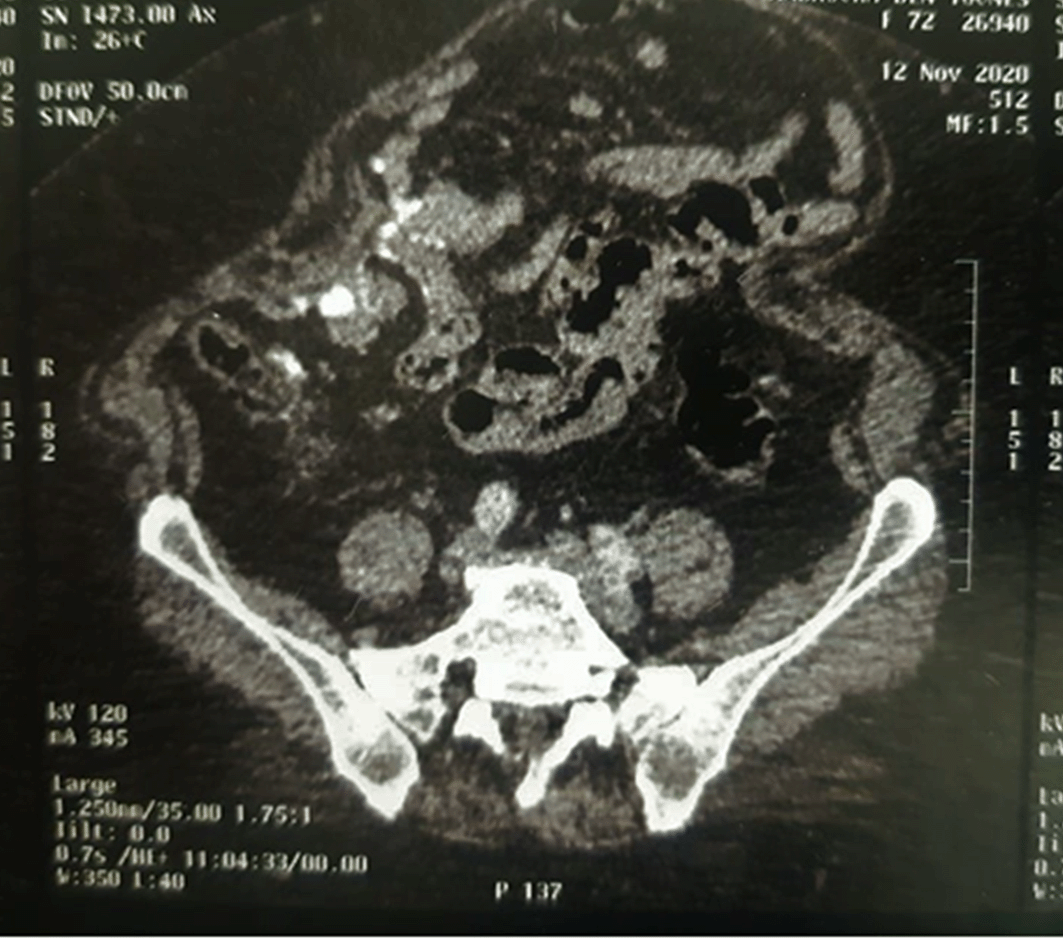

The patient was referred to gynecologic department for further investigation and to ascertain whether the tumor arose from ovaries or peritoneum. A computerized tomography scan was undergone and revealed: an uncomplicated sigmoid diverticulosis, an agglutination of the last ileal loops in contact with the anterior abdominal wall, an infiltration of the mesenteric fat and multiple mesenteric lymphadenopathies (see Figure 3). Hysterectomy, bilateral adnexectomy and omentectomy were performed. Macroscopic examination showed that both ovaries were intact having a normal size (see Figure 4). No invasion of ovarian stroma was shown in microscopic examination. No lymph node invasion or distant metastasis had been identified. The final diagnosis was primary peritoneal psammocarcinoma (PPP). It was classified as stage III C carcinoma according to the International Federation of Gynecology and Obstetrics’ (FIGO) classification.

Agglutination of the last ileal loops in contact with the anterior abdominal wall, infiltration of the mesenteric fat and multiple mesenteric lymphadenopathies.